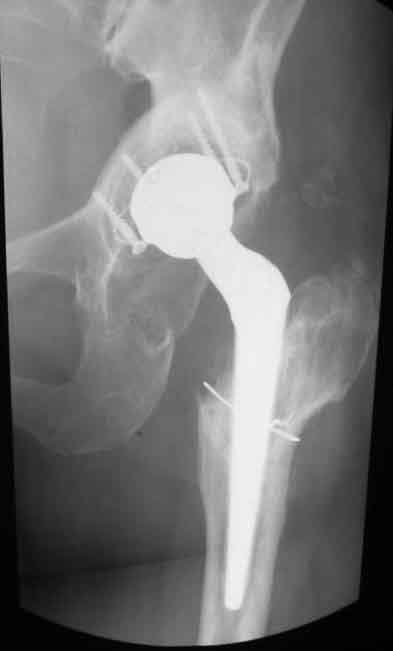

Уважаемые коллеги. Хотелось бы услышать мнения и советы по представляемому случаю.

Пациентка 45 лет. Бесцементное эндопротезирование левого тазобедренного сустава 6 лет

назад (впадина RM, Mathys, металл-металл, ножка Зульцеровская). За 10 лет до

протезирования коррегирующая остеотомия бедренной кости, которая не срослась в течение

года до удаления пластины, а затем срослась в течение 3 месяцев иммобилизации в кокситной

повязке. После протезирования получилось наблюдать пациентку почти постоянно, поскольку

через 2 года синтезировал ей лодыжки на оперированной стороне, затем, через несколько

месяцев удалил фиксаторы, а в 2009г. резецировал мениск на противоположной стороне. Боли

все эти годы не беспокоили. Пациентка чуть выше среднего роста, вес тела нормальный.

Физические нагрузки переносила хорошо. Работает на 7 этаже без лифта. Год назад экстирпация

матки по поводу лейомиомы больших размеров. Несколько месяцев назад появились боли в

области левого тазобедренного сустава. При рентгеновском и КТ исследованиях (июль с.г.)

нестабильность тазового компонента. От предложенной замены протеза пациентка на тот

момент, слава богу, отказалась. Через какое то время боли в области левого тазобедренного

сустава практически полностью прошли, а около 2 месяцев назад появилось ощущение

патологической подвижности таза и боли в паху справа, которые через некоторое время

уменьшились, а потом снова усилились после значительных физических нагрузок (много ходила

по песку на пляже, носила тяжести). Ежедневно принимала диклофенак. На рентгенограммах

переломы правой лонной кости. Сейчас госпитализирована из-за болей в паху справа. Боли

слева не беспокоят. На фоне снижения нагрузок в стационаре боли значимо уменьшились.

-Если думать о ревизии, то когда? На представленных снимках тазобедренный сустав до и

сразу после операции, затем 2 снимка 2009г., когда ничего не беспокоило, затем КТ 2-х

месячной давности и вчерашние рентгенограммы обоих тазобедренных суставов.